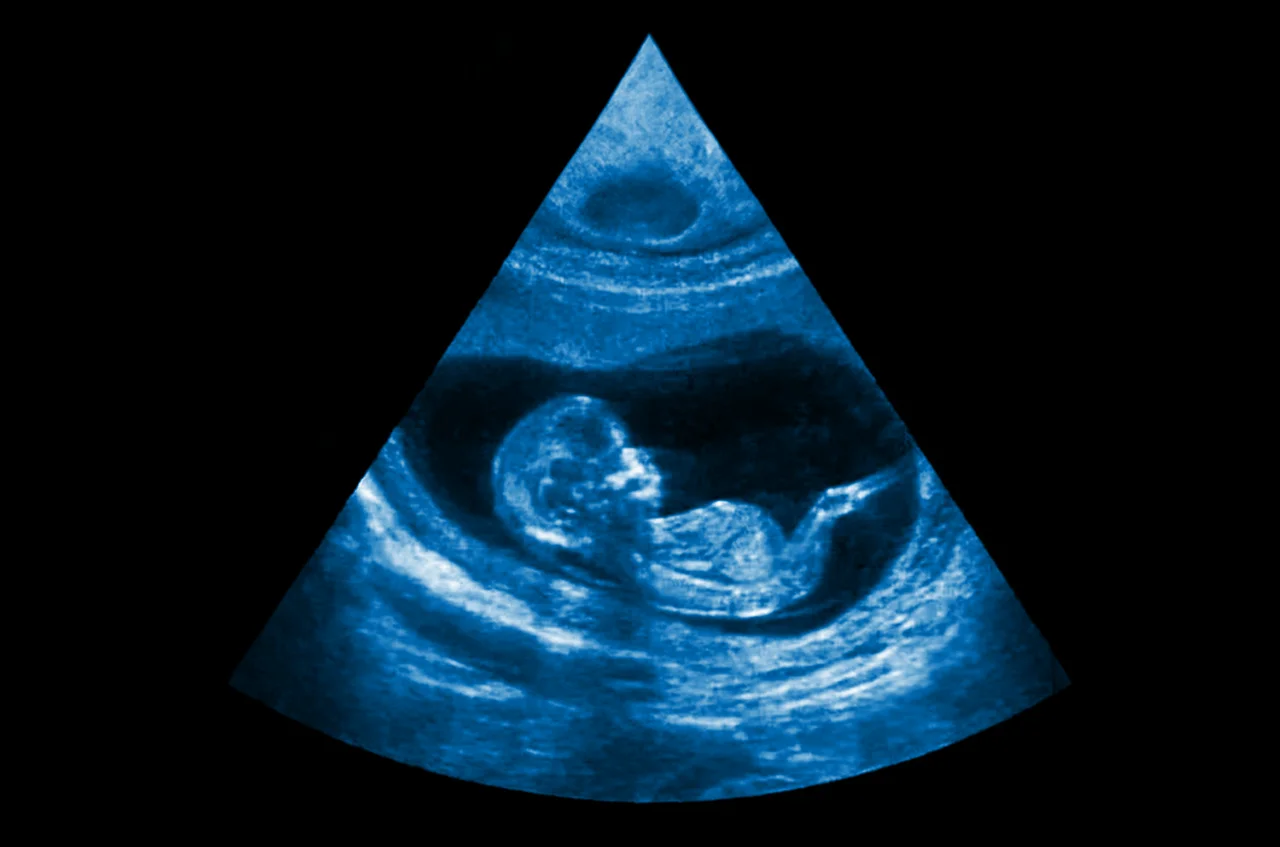

Confirmación por ultrasonido

El diagnóstico definitivo se alcanza mediante la ecografía transvaginal, generalmente entre la semana 5 y 6. Este estudio permite visualizar el saco gestacional y, poco después, el latido cardíaco. En esta etapa, el médico puede descartar complicaciones y brindar una calculadora de embarazo ajustada a la edad gestacional real. Confirmar la ubicación intrauterina del embrión transforma la sospecha inicial en una certeza clínica, permitiendo a la paciente transitar el resto del proceso con seguridad y bajo supervisión profesional.